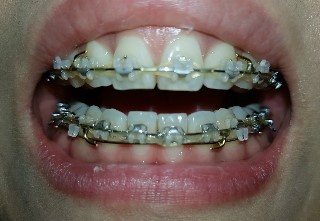

교합 마무리 조언 부탁드려요~~~

안녕하세요 위아래 앞니는 이미 교정기도 거의다 뗀 상태고 어금니 쪽에만 교정기가 몇개 남아 있는데 교합 때문에 고민이 많아 매일 잠 못들고 있어서 선생님께 도움 요청 드립니다. ㅠㅠ 일단 첨부한 사진상으로 보...